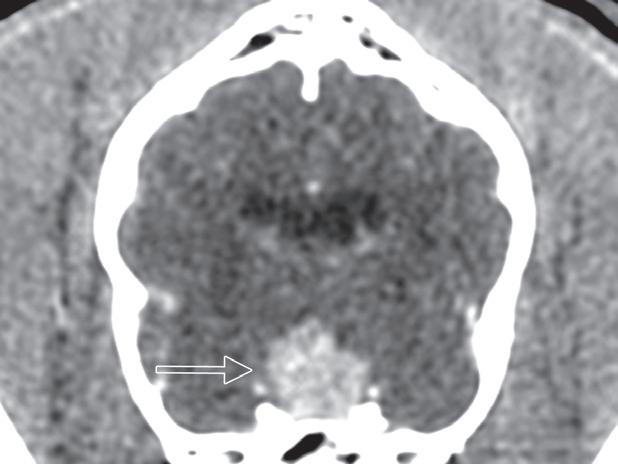

Rycina 5.6.6. Przysadkowozależna nadczynność kory nadnerczy (pies) TK

Badanie wykonano u 12-letniego, kastrowanego boston teriera z podejrzeniem przysadkowozależnej nadczynności kory nadnerczy. W badaniu natywnym oba nadnercza (a, b – strzałki) są powiększone i zaokrąglone, a także wykazują jednorodną densyjność tkanek miękkich. Widoczna jest mineralizacja ściany tętnicy krezkowej przedniej, która jest zmianą wtórną do zespołu Cushinga (b – gwiazdka). Obraz po podaniu dożylnego środka kontrastowego mózgowia ujawnia duży, intensywnie wzmacniający się rozrost przysadki (d – otwarta strzałka), przypuszczalnie o charakterze funkcjonalnym